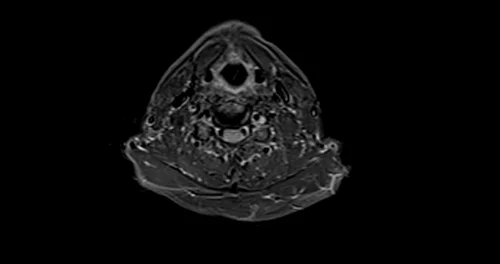

MRI brachial plexus axial STIR images